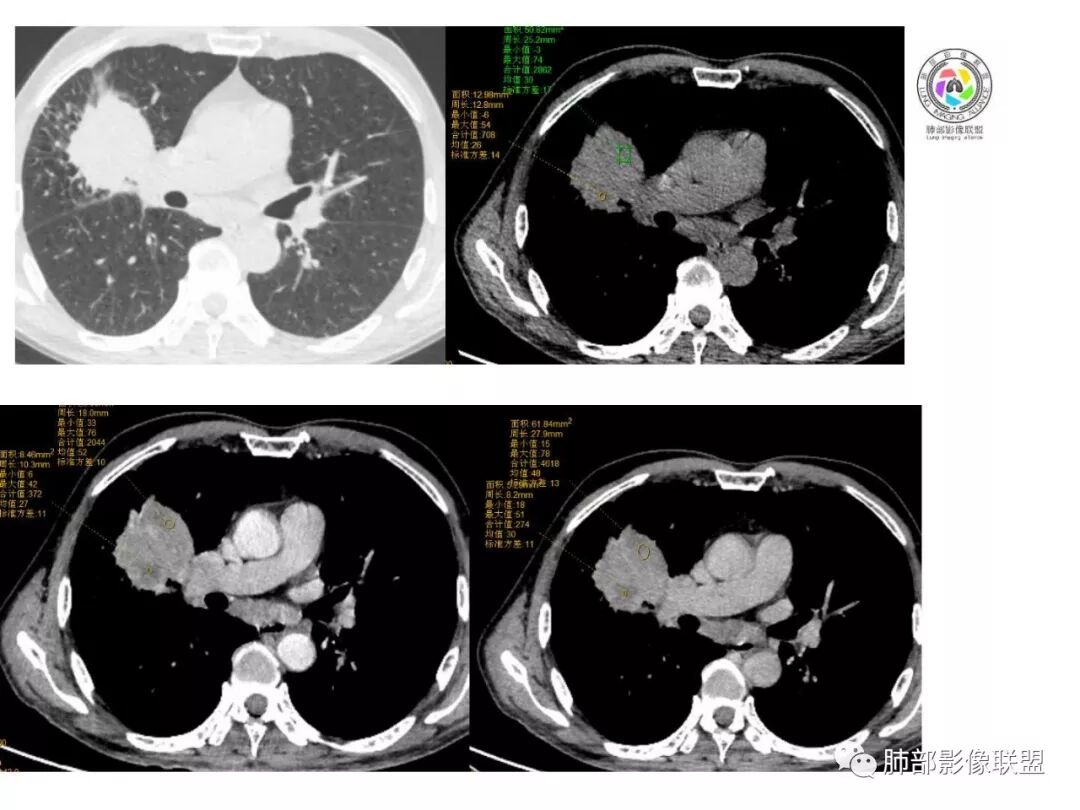

右肺巨大肿块,跨叶生长,其内见大片状坏死,坏死边界不清,血管进入,边缘受侵,病灶边缘可见毛刺及分叶,病灶强化方式速升速降,纵隔内见坏死强化淋巴结,周围肺叶小叶间隔结节样增厚,考虑恶性腺癌并淋巴结转移及癌性淋巴管炎,鉴别肉瘤。

右肺中叶可见类圆形软组织密度肿块影,右肺中叶外侧段支气管狭窄截断。肿块密度不均,边缘毛燥不规则,可见毛刺。远侧肺内可见网格条索影。增强后可见不均匀强化。纵隔淋巴结肿大,部分融合。考虑右肺恶性病变,鳞癌>腺癌,并纵隔淋巴结转移。

患者中老年男性,体检发现肺部占位。

胸CT:右肺中叶实性占位性病变,呈膨胀性生长,对斜裂明显挤压,右肺中叶外侧段阻塞,并在边缘可见分叶、毛刺、棘突样改变,胸膜牵拉;增强可见病灶明显强化,可见边缘模糊血管影,病灶内可见大片状低密度区,隆突下可见肿大淋巴结。

诊断考虑:恶性病变。

右肺巨大肿块,横跨上中下三叶,主体在中叶,外侧段近端支气管截断,膨隆分叶,毛刺,网格,淋巴结大,不均匀强化,湖泊样坏死,考虑恶性,低分化鳞癌>腺

右肺肿块,横跨上中下三叶,主体在中叶,外侧段近端支气管截断,膨隆分叶,毛刺,网格,淋巴结大,不均匀强化,有坏死,鳞癌?

老年男性,查体发现,右肺上叶中叶巨大肿块,有分叶,周围有条索影,支气管受压推移,内有大片及小灶坏死,坏死边界有的清楚有的不清,周围明显强化,纵隔有肿大淋巴结,跨叶生长,考虑恶性,腺癌或肉瘤样癌

右肺中叶可见类圆形软组织密度肿块影,支气管狭窄截断。肿块密度不均,边缘毛燥不规则,可见毛刺。增强后可见不均匀强化。纵隔淋巴结肿大,部分融合。考虑右肺恶性病变,鳞癌?

老年男性,右肺上叶可见一团块影,边界清,有膨隆,有凹陷,棘突,有分叶,密度不均匀,周边可见癌性淋巴管炎,跨叶裂,支气管阻塞?受压?狭窄,纵隔淋巴结肿大,考虑恶性,腺癌可能

右肺跨上叶与中叶一实性肿块影,中叶外侧段支气管堵塞,肿块有明显分叶、毛刺、棘突样改变,胸膜牵拉,周围有小花小草;增强可见病灶明显强化,病灶内可见大片状低密度区,以外侧为主,隆突下可见肿大淋巴结,恶性,考虑鳞癌可能。

老年人,右肺上叶软组织肿块,边界清晰,有浅分叶,右肺上叶支气管受阻,增强后病灶边缘强化,内部似有延迟强化,内见血管造影征,其血管边缘毛糙,纵隔可见增大淋巴结,考虑恶性肿瘤,无明显阻塞性肺炎和不张,考虑腺癌或腺鳞癌伴纵隔淋巴结转移

老年男性,体检发现右肺巨大肿块,右肺跨叶生长,可见支气管截断,边缘见分叶,毛刺,右肺支气管不通,增强后边缘强化,内部示大片低密度坏死区,边界不清,周围肺组织小叶间隔增厚,纵隔见多发肿大淋巴结。考虑为恶性并淋巴结转移。

右肺肺门肿块,自肺门向外延伸,外大内小,肿块呈长条状,平行支气管,近段支气管不规则堵塞,支气管无扩张壁无增厚,平扫密度均匀,增强后可见不规则坏死,病灶跨叶裂生长,纵隔淋巴结肿大,中老年男性,体检发现,无症状,考虑:恶性鳞癌,鉴别结核

老年男性,右肺跨裂生长团块灶,边缘浅分叶,内不均匀强化,无强化坏死区较多,可见支气管截断,周围阻塞性炎症,考虑恶性肿瘤可能,慢性肺脓肿待排

老年男性,右肺不规则跨叶肿块,有分叶,相邻支气管阻断,强化不均有低密度坏死区,坏死区边界较清,类似湖泊样,内见血管穿行,造影征,病灶远端可能有阻塞性炎症,总体考虑鳞癌。

患者中老年男性,体检发现右肺占位。血常规轻度贫血,AFP、CEA正常,肝肾功能、血糖、血脂、心肌酶、电解质正常。胸部CT:右肺中叶巨大肿块灶,垮叶生长,可见分叶、毛刺、血管集束、支气管截断征象,远端周围可见小叶间隔增厚,增强轻度强化,内可见低密度坏死区,综合淋巴结肿大,且可见淋巴结内似低密度灶。综合考虑恶性,鳞癌并癌性淋巴管炎可能大。鉴别结核、腺癌。

胸CT:右肺中叶团块样实性占位,边缘膨隆,中叶外侧段阻塞,病灶可见深分叶、棘突,胸膜牵拉;增强不均匀强化,可见边缘模糊血管影,病灶内大片状低密度区,纵隔多发肿大淋巴结。

诊断考虑:恶性病变,鳞?大细胞?鉴别:TB

右肺中叶巨大肿块,外侧段近端支气管截断,横跨上中下三叶,主体在中叶,膨隆分叶,毛刺,网格,淋巴结大,不均匀强化,伴阻塞性肺炎及肺不张,湖泊样坏死,考虑恶性,鳞癌可能性较大

右肺上叶肿块,跨叶生长,分叶,支气管截断,周围支气管受压推移,内有大片坏死,周围小叶间隔增厚,纵隔淋巴结肿大,明显强化,考虑肉瘤样癌。鉴别腺鳞癌。

病灶主体位于右肺中叶,跨上、下叶,分叶毛刺,外侧段支气管堵塞,大片坏死,边界不清,内见血管进入,增强快进快出,纵隔淋巴结肿大,小叶间隔增厚,恶性,腺癌或肉瘤样癌可能。

右肺门旁肿块,形态不规则,跨叶生长,近段支气管不规则堵塞,支气管局部增厚,密度欠均匀,增强后可见不规则坏死,纵隔淋巴结肿大,中老年男性,体检发现,考虑:恶性鳞癌